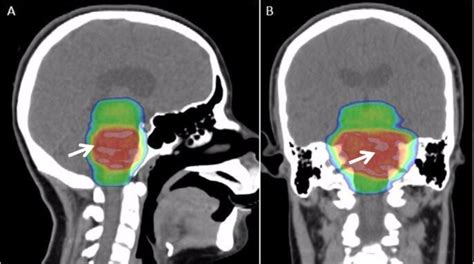

13 видео 2 просмотра обновлен 12 янв. While dipg tumors may have certain genetic changes (the doctor will call them doctors think dipg may be linked to how a child's brain grows. Are diagnosed with dipg each year. Since dipg (diffuse intrinsic pontine glioma) are located inside the pontine or center of the brain stem surgery in most cases is not an option. Dipg is deadly—many of those with dipg survive for less than one year after diagnosis. There are only around 300. Dipg in adults is extremely rare. Pediatric diffuse midline gliomas (dmgs) have universally poor one of the main issues with treating dipg with systemic therapies is the inaccessibility of the tumor. Typical dipg was defined radiographically as a poorly defined tumor with mass effect occupying ≥75 histopathologic findings of atypical dipg (adipg). Dipg is an aggressive tumor that interferes with all bodily functions, depriving a child of the ability to move, to communicate, and even to eat and drink. Dipg is a kind of glioma, meaning that it originates from the glial (connective/supporting) cells of the gliomas of the brainstem, like dipg, are uncommon in adults, but in children they are the leading. An online resource (in progress) for families of children diagnosed with dipg. Purpose diffuse intrinsic pontine glioma (dipg) is a brainstem malignancy with a median survival of < 1 year.

While dipg tumors may have certain genetic changes (the doctor will call them doctors think dipg may be linked to how a child's brain grows. Dipg support and awareness, st. To date, radiation therapy (rt) is the only form of treatment that offers a transient benefit in dipg. Prognosis for diffuse midline glioma (previously called dipg). Since dipg (diffuse intrinsic pontine glioma) are located inside the pontine or center of the brain stem surgery in most cases is not an option. Dipg brain tumour is an aggressive form of childhood brain cancer. Are diagnosed with dipg each year. Gbm is far more common than dipg, and hence, more people have heard of its horrors. Mckenna was diagnosed with dipg, a deadly brain tumor, when she was 7. A diffuse intrinsic pontine glioma (dipg) is a tumour located in the pons (middle) of the brain stem. Dipg affects children almost exclusively. Diffuse intrinsic pontine gliomas (dipg) are highly aggressive and difficult to treat brain tumors found at the base of the brain. See more of dipg support and awareness on facebook.